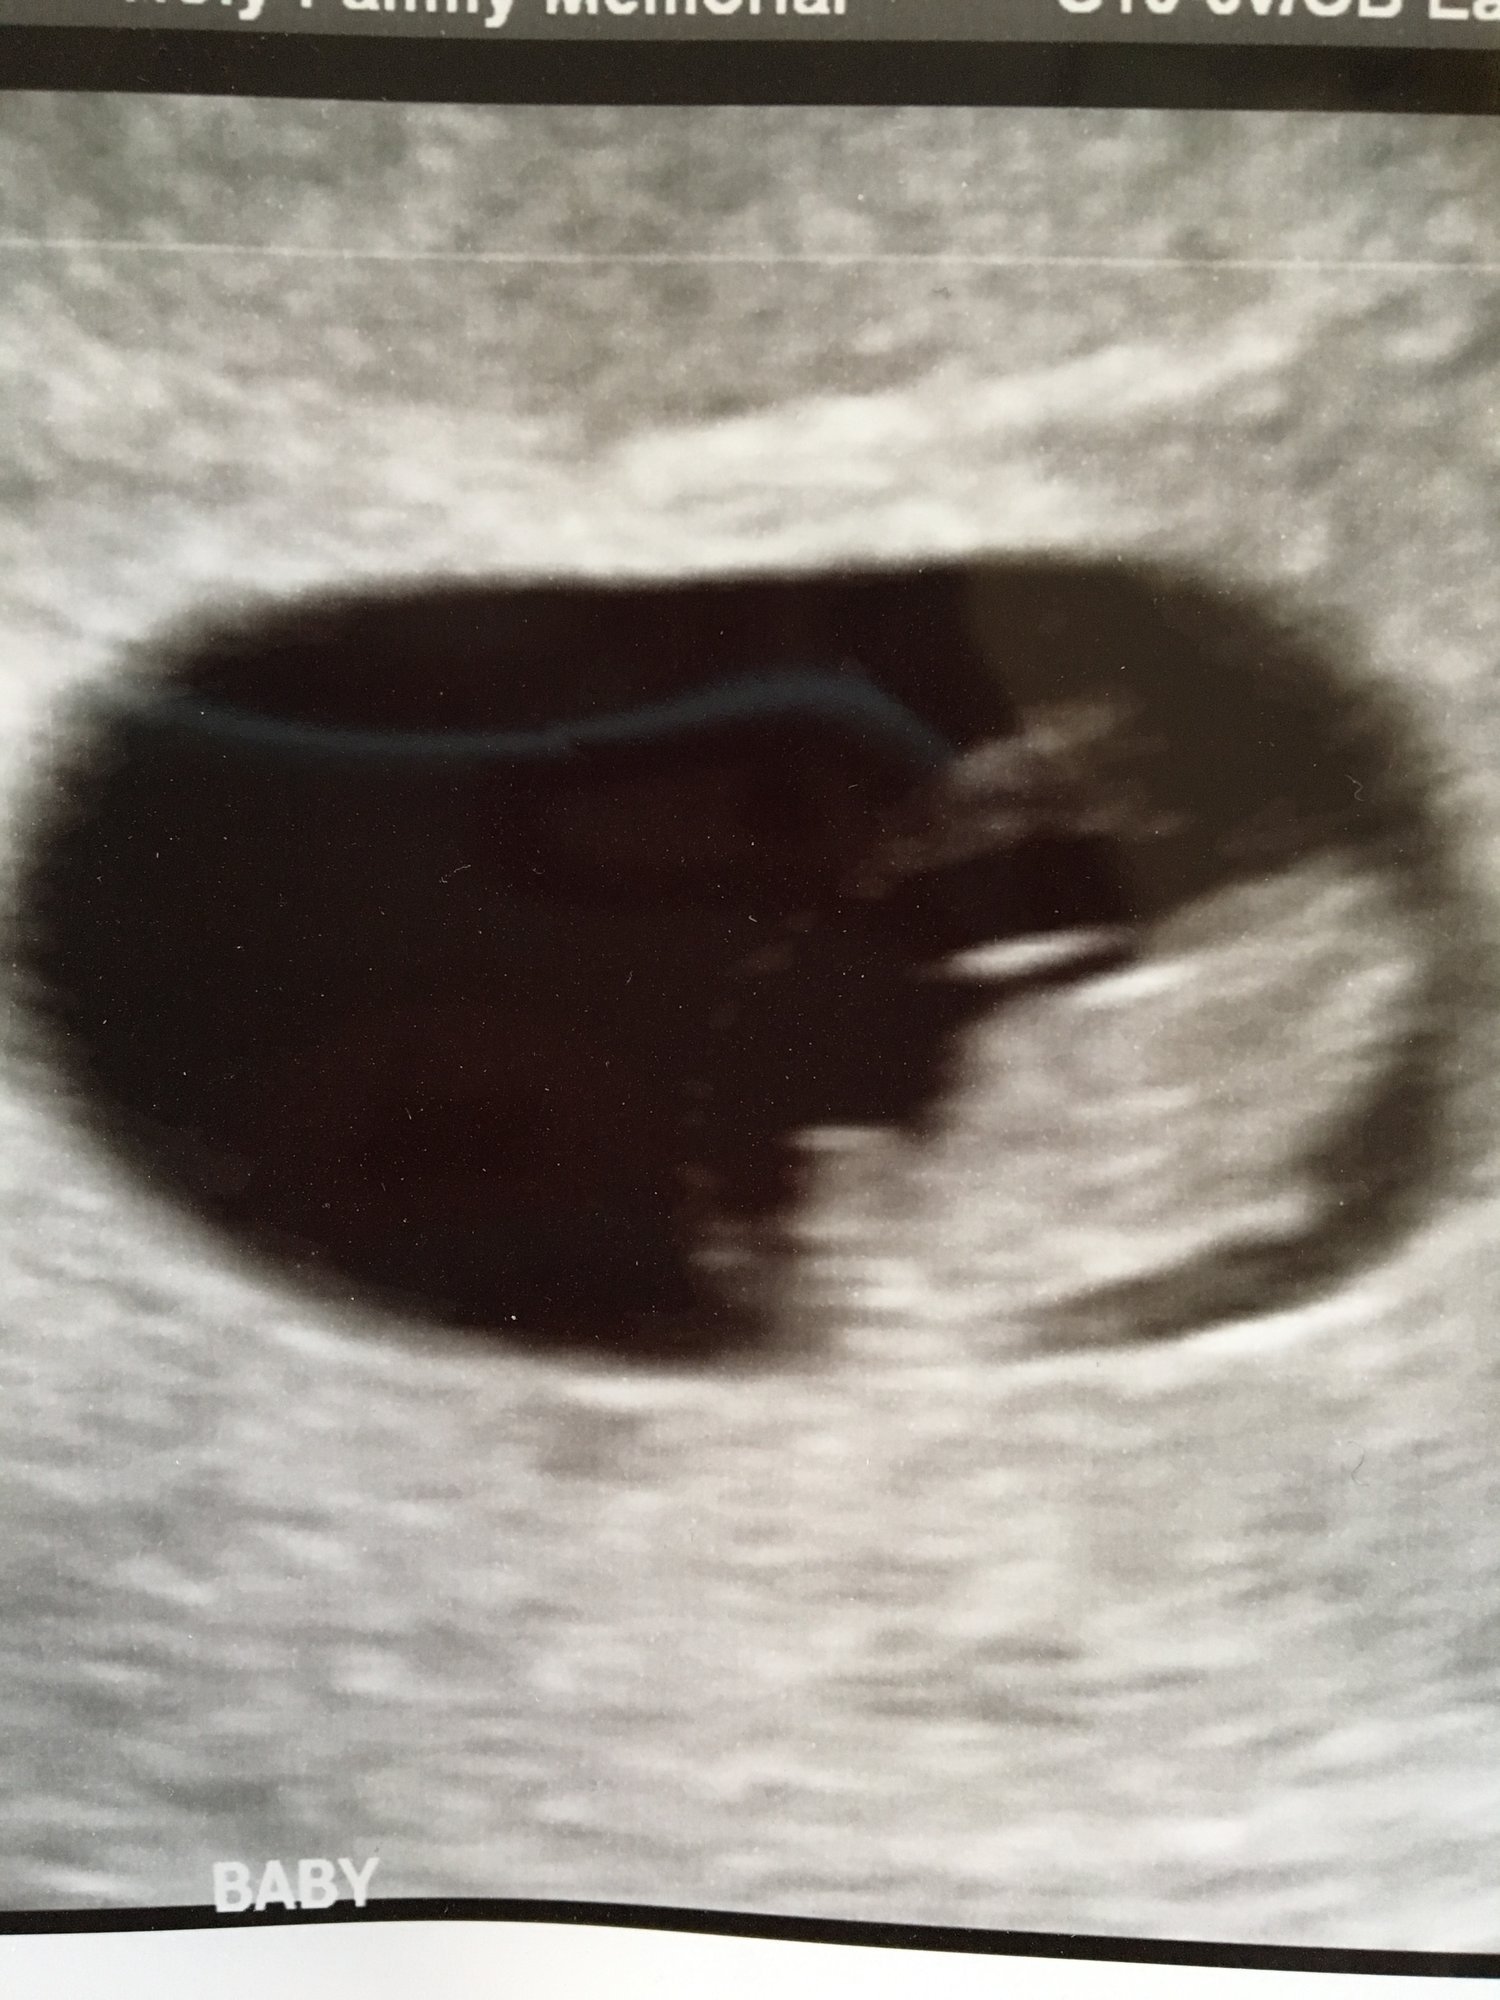

I feel so relieved! Doctor said everything looked great and we saw the heart beat